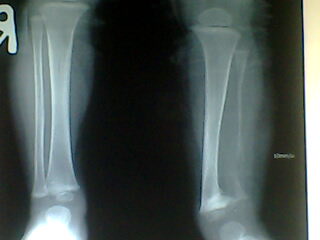

标题: PED0257:小腿

小孩腿痛波形

腓骨骨质溶解,大块骨质溶解症可能性大,建议进一步询问病史,进一步检查。有既往片价值更高。

左腓骨呈容骨性破坏。骨皮质及骨髓腔均破坏,下段骨不连续,周围软组织肿胀。考虑骨尤文氏肉瘤可能性大。

尤文肉瘤的明显软组织肿块与较小骨质破坏不成比例,本例似乎不符合。应考虑腓骨骨质溶解,建议询问家族史。